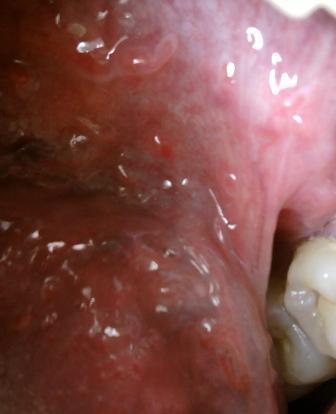

尖锐湿疣还能根治吗尖锐湿疣是一种因人乳头样病毒(HPV)感染造成的恶性性传播疾病,这种疾病非常容易反复,且迁延不愈。我们,都知道不注意性卫生会引起尖锐湿疣。尖锐湿疣病情恶化之后会严重影响患者的健康。尖锐湿疣并不是什么难以启齿的疾病,一旦患病要及时就医,同时也要注意保持良好的生活习惯,抵制性乱。积极乐观的心态对于疾病的治疗和恢复也是很关键的。